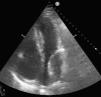

Varón de 80 años, con múltiples factores de riesgo cardiovascular, que ingresa en la unidad de cuidados intensivos por infarto agudo de miocardio sin elevación del segmento ST. Se realiza coronariografía que muestra enfermedad coronaria de tronco izquierdo y descendente anterior que se revasculariza mediante implante de 2 stent farmacoactivos solapados (fig. 1, flecha azul). Para el procedimiento se sonda con una guía la arteria circunfleja (fig. 1, flecha roja). La intervención transcurre sin incidencias, comenzando el paciente tras esta de forma brusca con clínica de insuficiencia cardiaca. Se realiza ecocardiografía transtorácica que muestra a nivel inferior de la aurícula izquierda una masa de 64×40mm de contornos bien definidos e interior ecolúcido con el tamaño reducido de dicha cavidad que compromete el llenado auricular, compatible con hematoma de pared auricular izquierda (fig. 2).